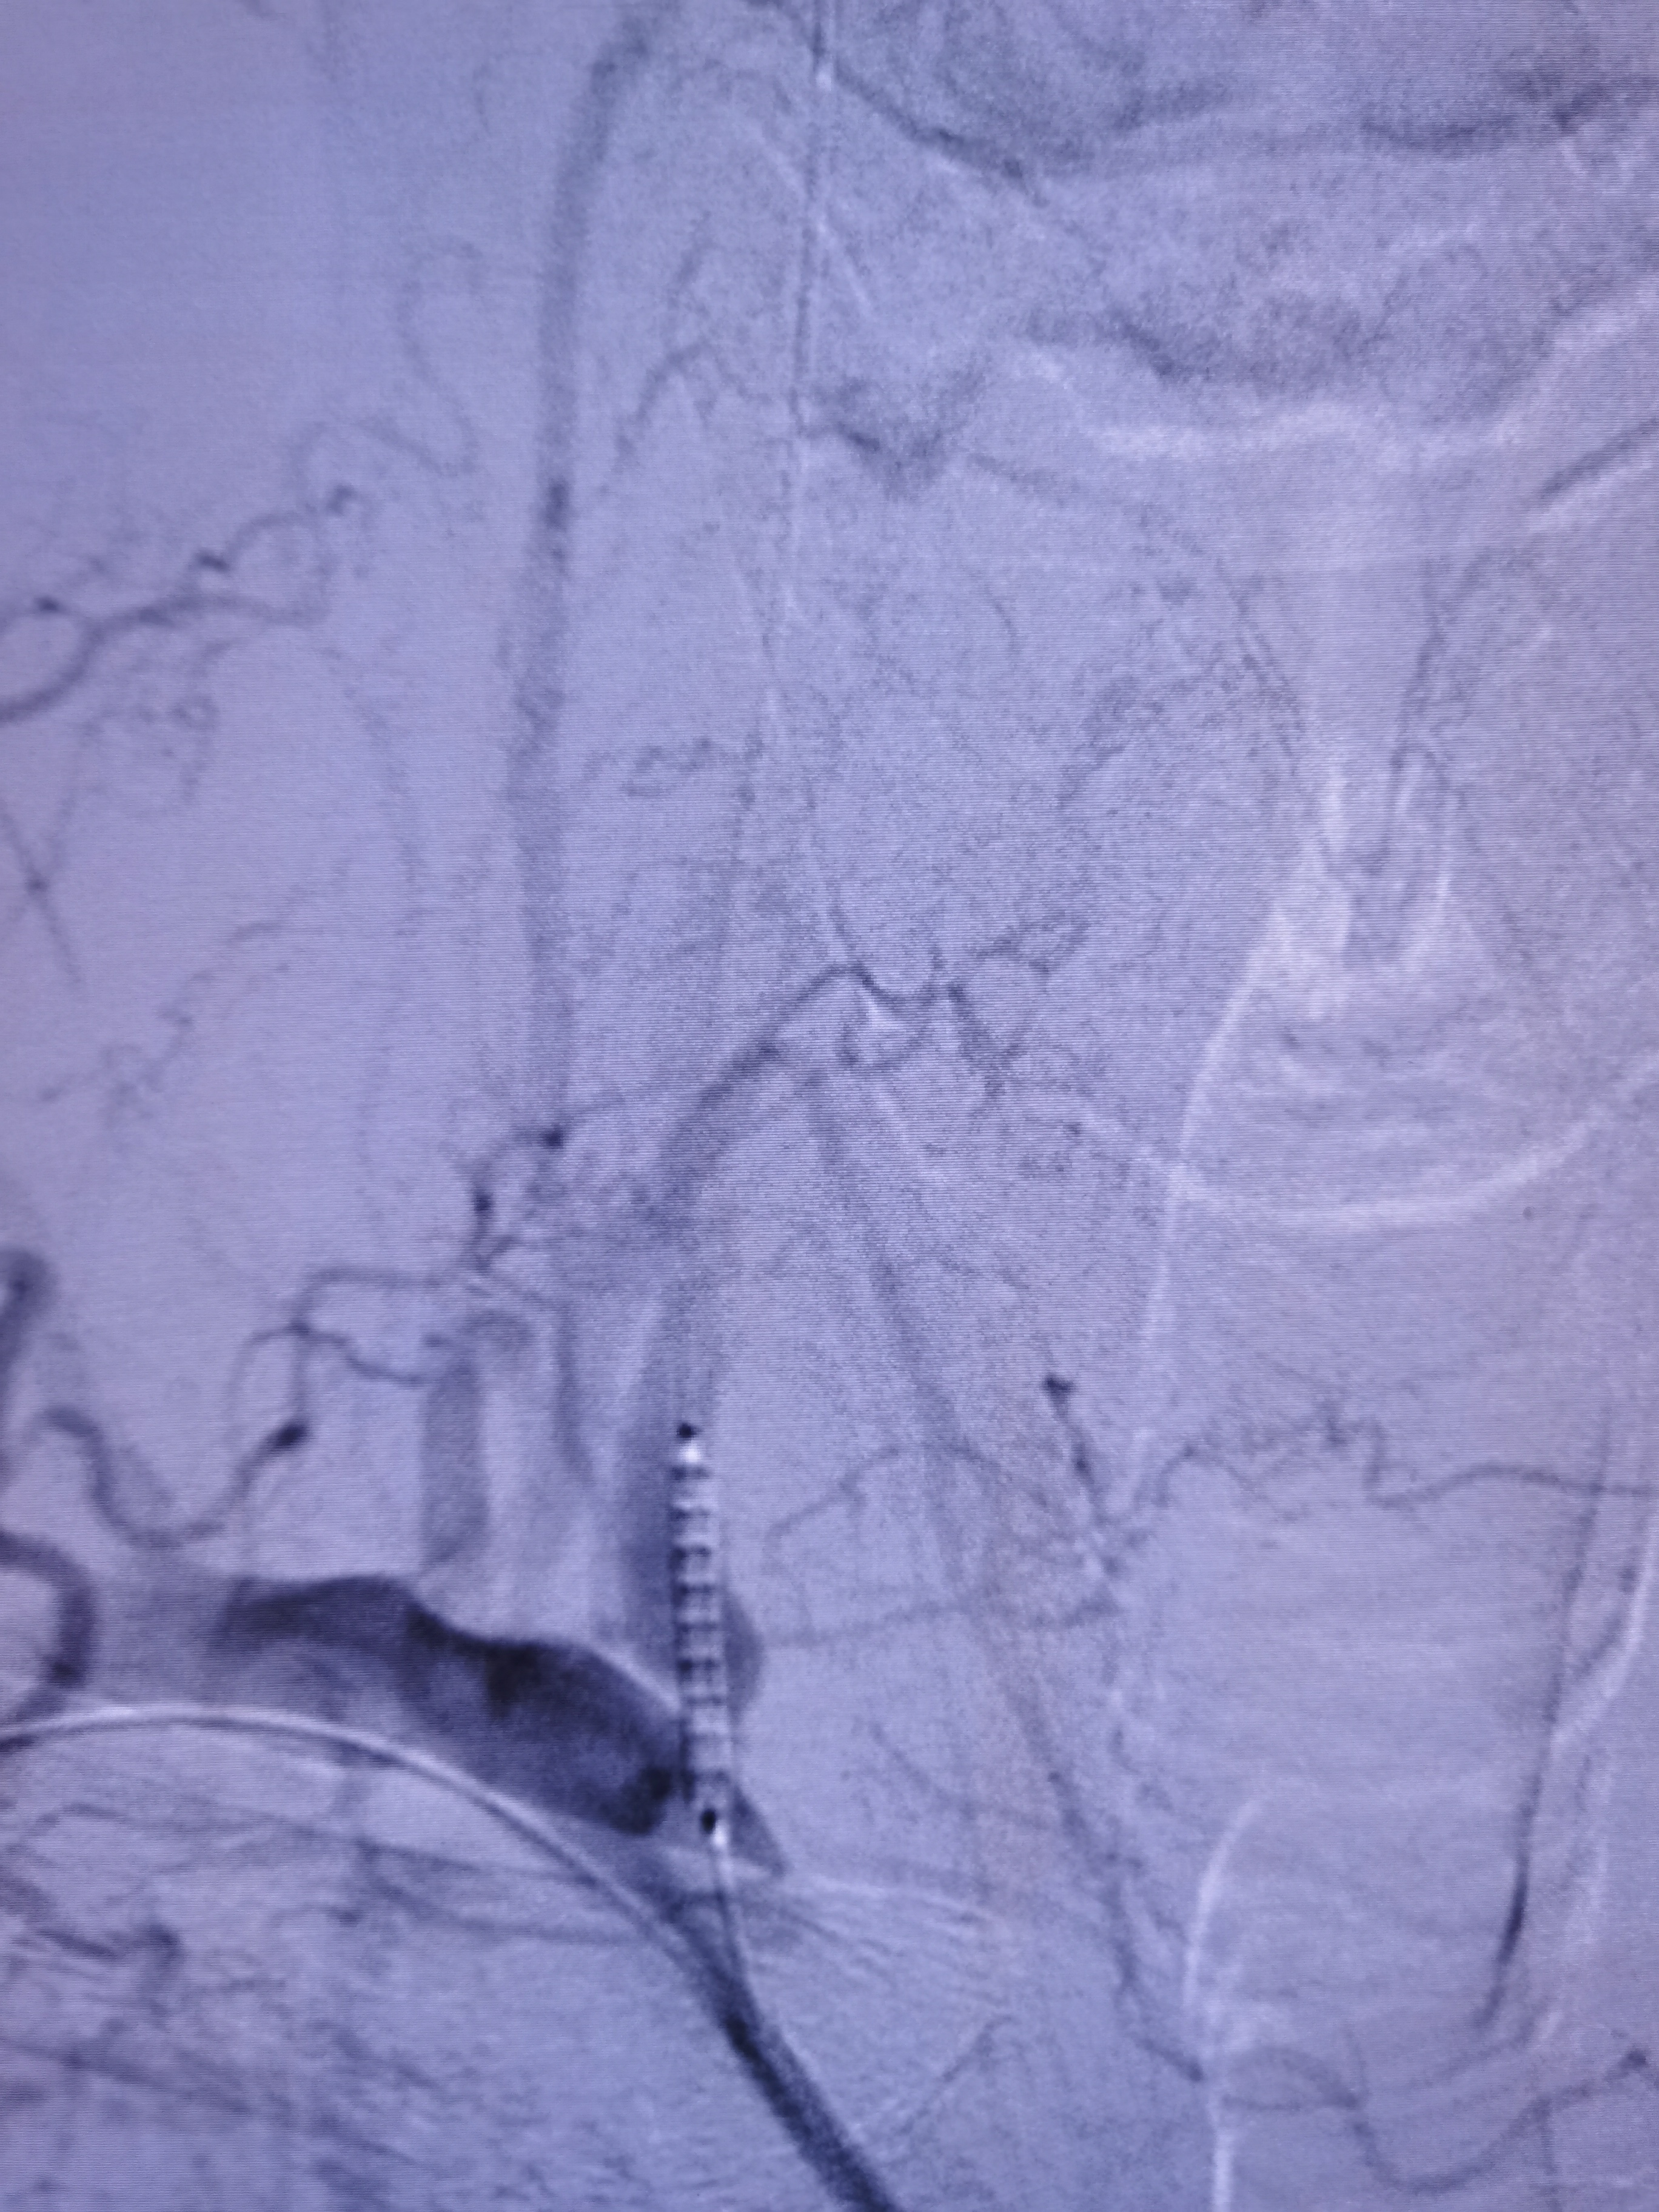

5.0/15支架定位

支架释放后狭窄解除

将导引导管调至右侧颈总末端,送入远端保护伞,4/30球囊预扩。

7-9/40支架定位

支架释放后狭窄改善,考虑患者高龄,颅内动脉硬化,担心术后高灌注出血,遂未再进行大球囊后扩。

撤出保护伞,造影见狭窄改善明显。